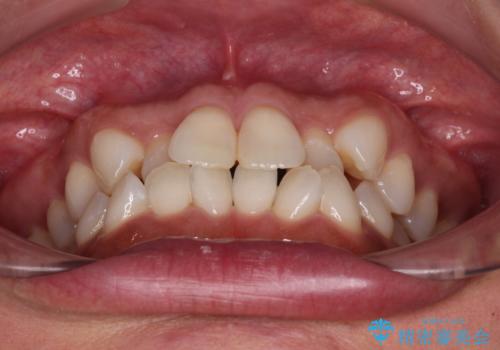

前歯のクロスバイト インビザラインによる矯正治療

- 上下のクロスバイトと前歯のデコボコを気にして来院された患者様です。

インビザラインを用い、IPR(歯と歯の間を削る)と歯列全体を拡大させることで、歯並びを整えていくこととしました。